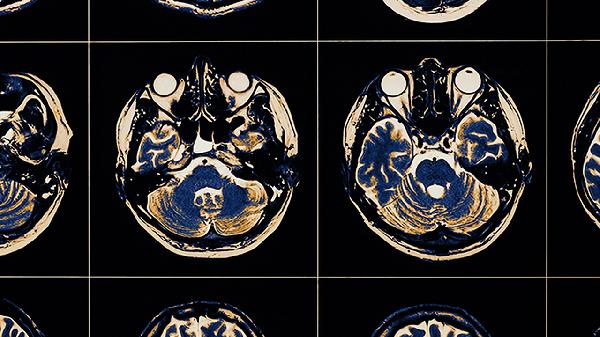

脑血栓病发的前兆主要有短暂性脑缺血发作、突发性头痛、肢体无力或麻木、言语障碍、视力异常等。脑血栓通常由动脉粥样硬化、高血压、糖尿病、心房颤动、血液高凝状态等因素引起,可能表现为头晕、恶心、平衡失调等症状。

突然出现的表达困难、词不达意或听不懂他人说话,提示优势半球语言中枢缺血。此类症状常与基底节区或颞叶梗死相关,需通过头颅CT或MRI明确病灶。康复期可结合语言训练,并遵医嘱使用胞磷胆碱钠胶囊营养神经,配合银杏叶提取物片改善脑微循环。